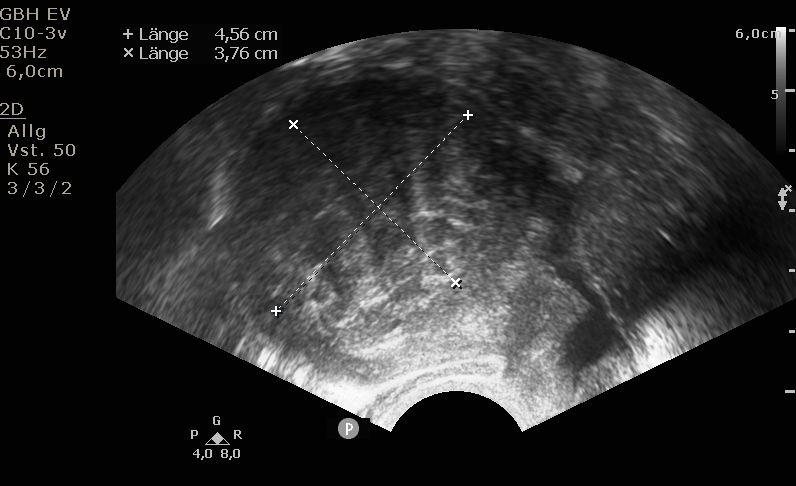

Die Diagnosestellung erfolgt in aller Regel mittels transvaginalem (durch die Scheide) Ultraschall. Nur in Ausnahmefällen ist eine MRT-Untersuchung notwendig.

Bei der Gebärmutterspiegelung wird die Gebärmutterhöhle mit Kochsalzlösung aufgedehnt. Eine Kamera mit integrierter Elektroschlinge wird in die Gebärmutter eingeführt. Die vorhandenen Myome können nun schrittweise unter Sicht abgetragen werden. Mittels modernsten Ultraschalluntersuchungen werden die Myome während der Operation noch einmal genau dargestellt. Bei sehr großen Befunden können zwei Operation zur kompletten Myomentfernung notwendig sein.

In Tübingen gehen wir mit den neuesten Entwicklungen der Medizin. So bieten wir auch die transzervikale Radiofrequenzablation (Sonata®) zur Myomverkleinerung an. Bei dieser Technik wird durch Einbringen einer speziellen Sonde durch den Gebärmutterhals das Myom per Ultraschall dargestellt und gezielt mit einer speziellen Elektrode punktiert. Über diese Elektrode wird mittels Strom Hitze erzeugt, die das Myom nachhaltig zerstört. Das geschädigte Myom wird in den folgenden Monaten vom Körper abgebaut und damit kleiner.